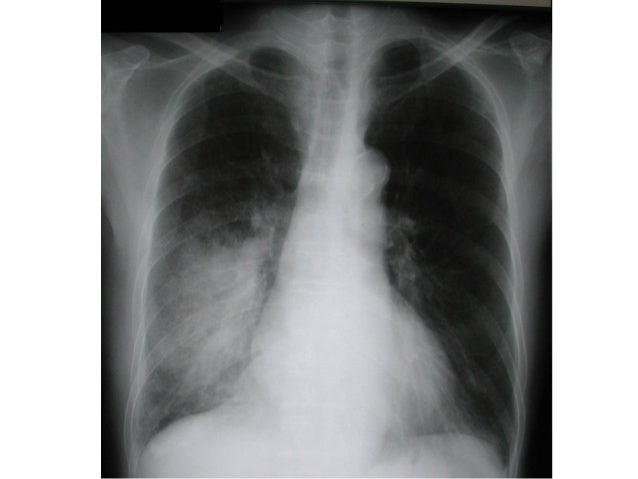

Schatzki ring treatment & management. A schatzki ring is a band of tissue that can develop at the lower end of the food pipe. The schatzki ring was first identified in asymptomatic people in. Schatzki's ring in lower esophagus with difficulty swallowing.